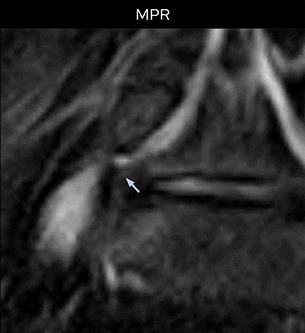

“Recently, the two surgical methods extreme and oblique lateral interbody fusion (XLIF and OLIF) have become mainstream for minimally invasive treatment of lumbar spinal canal stenosis and intervertebral foramen stenosis. With these surgical techniques, the spine is approached from the flank, and prior knowledge of the exact anatomy of the lumbosacral plexus would be extremely helpful. To that end, high slice resolution (less than 1 mm acquisition) that enables sharper sagittal MPR images will be needed.”

“For both brachial and lumbar plexus, we are currently using a 230 mm FOV and voxels of about 1 x 1 x 2 mm acquired (1 x 1 x 1 mm reconstructed). This provides us a good representation of the nerves, even though this FOV is relatively small. Regarding the inplane resolution, we hope to be able to bring that down to 0.7 mm, similar to our typical 2D multislice T2W images,” says Tanji.